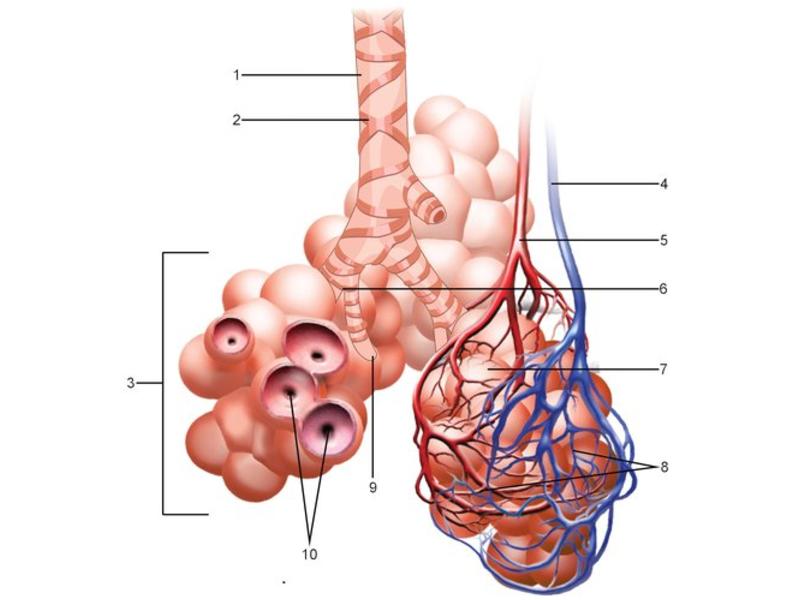

Go with the flow

Trace the air flow of respiratory system starting with the nostrils.What path does a molecule of oxygen take to reach the blood?

What sights will it see along the way?

The cardiovascular system needs to be connected to the respiratory system.Path of O2 and CO2

Bronchi - Transitions

- Intrapulmonary bronchi

- Irregular cartilage

- Respiratory epithelium

- Glands

- Bronchioles

- Smooth muscle REPLACE cartilage

- Ciliated columnar > Ciliated cuboidal

- NO glands - goblet cells -> secretory cells

- Terminal bronchioles

- Smooth muscle

- Ciliated cuboidal epithelium

- Secretory cells

- Respiratory bronchioles

- Conducting -> Respiratory

- Simple cuboidal epithelium

- Secretory cells

- Alveoli

Lungs